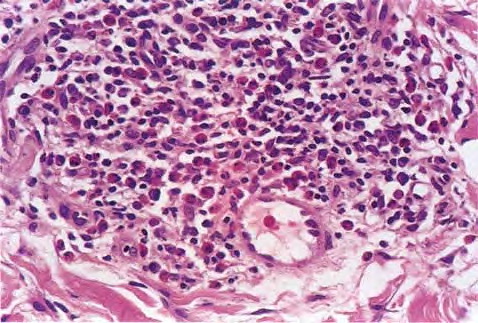

Read MoreParaffinoma = الورم البارافيني Paraffinoma Foreign-body reactions may occur following injections of oily substances such as mineral oil (paraffin) typically into the breasts , genitalia, or scalp for cosmetic purposes. These occur as irregular, plaquelike indurations of the skin and subcutaneous tissue . Ulcers or abscesses may develop. The interval between the time of injection and […]